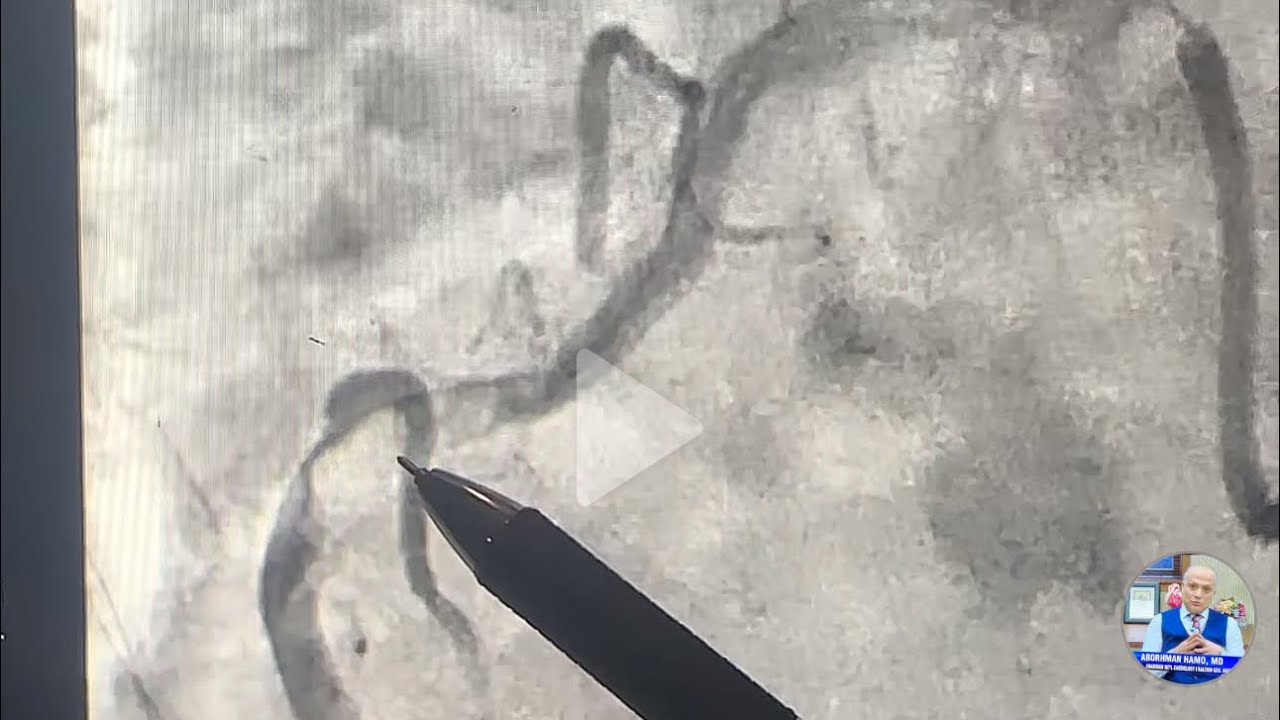

Скачать или смотреть Обширный инфаркт миокарда с подъемом сегмента ST. 100% окклюзия левой главной коронарной артерии/...

Обширный инфаркт миокарда с подъемом сегмента ST. 100% окклюзия левой главной коронарной артерии/...